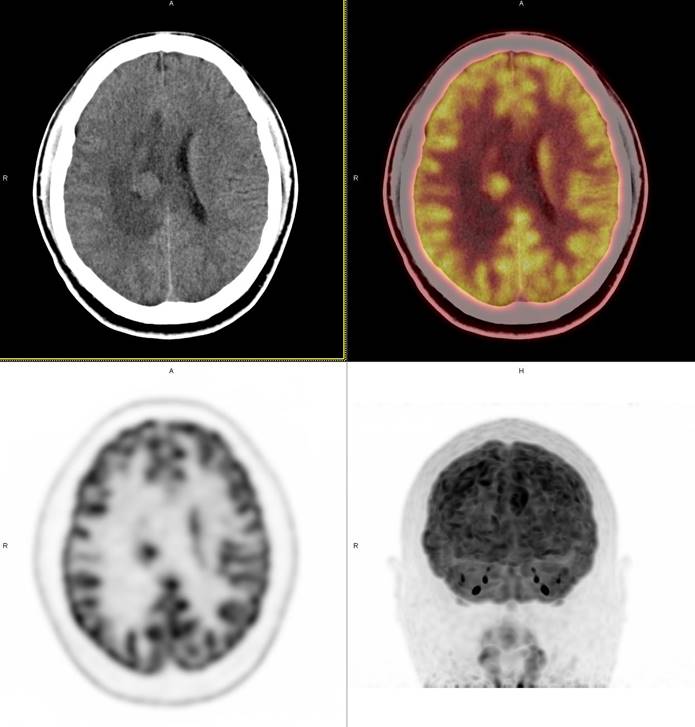

PET/CT影像圖

圖1

圖2

圖3

圖4

PET/CT檢查

影像診斷: 右側(cè)側(cè)腦室旁腦實質(zhì)內(nèi)結節(jié),代謝異常增高(SUVmax 12.13),伴瘤周水腫。

病理診斷:腦膜瘤二級

此例,PET/CT全身檢查不僅排除了轉(zhuǎn)移瘤的可能性,增高的SUV值無創(chuàng)地鑒別腦膜瘤的良惡性,充分體檢PET/CT大視野、形態(tài)與功能影像結合的優(yōu)勢。